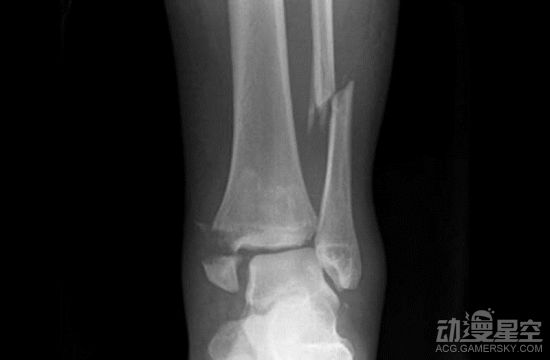

之前我们报道了一位新加坡的小哥使用《一拳超人》中埼玉老师的锻炼方法进行身体塑形,一个月下来效果显著。不过每天100个俯卧撑、100个深蹲和跑步10公里真的不是小运动量,如果之前没有基础很可能会出现各种问题。近日又有一名来自马来西亚的男子用这个方法来减肥塑身,2个月之后虽然成功的减下13公斤,但是却导致自己骨折了。 ![]() 有网友在推特上发文称看到同事用这种方法锻炼,结果很惨烈:“同事在两个月内做了《一拳超人》中的训练,从78公斤减到65公斤,不幸的是他踝关节骨折需要休息8周。这种锻炼每天都得做,对身体的负担很大,我想说你得了解自己的身体状况而不是直接照做啊。” ![]() 虽然成功减重,但是锻炼2个月之后需要休息2个月,估计效果全都没了。不知道这个马来西亚男子在痊愈之后还敢不敢接着疯狂锻炼,希望他下次还是选用符合自身情况的锻炼方法。连埼玉老师秃了才能变强,这个方法还是要量力而行啊。 (编辑:温州站长网) 【声明】本站内容均来自网络,其相关言论仅代表作者个人观点,不代表本站立场。若无意侵犯到您的权利,请及时与联系站长删除相关内容! |